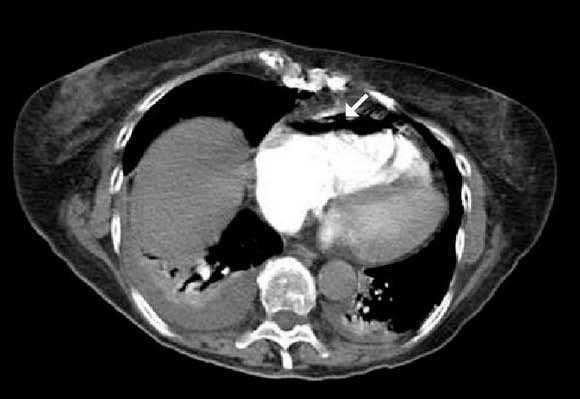

Figura 2.

Mujer de 75 años con antecedente de tromboembolismo pulmonar (TEP) y anticoagulada que ingresa por hematoma retroperitoneal espontáneo. Presenta hemoglobina de 4,8 g/dl e hipotensión, canalizándose dos vías venosas periféricas para reanimación con volumen y hemoderivados. Tras 48 horas desarrolla insuficiencia respiratoria aguda (PaO2/FiO2: 92), y ante la sospecha de nuevo TEP se realiza tomografía axial computarizada (TAC) de tórax, que evidencia aire en vena cava, arteria pulmonar y cavidades cardíacas derechas (figs.1 y 2). Ingresa en la Unidad de Cuidados Intensivos, donde es colocada en decúbito lateral izquierdo y se le administra O2 al 100% y tratamiento de soporte. Se intentó la aspiración del aire por vena subclavia derecha, sin objetivar salida de burbujas. En la TAC de control se comprobó la ausencia de aire en la vena cava, arteria pulmonar y cavidades derechas. La paciente fue dada de alta al tercer día con PaO2/FiO2 de 200.